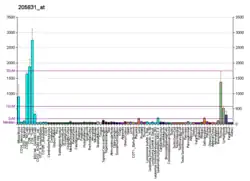

- Human CD2 genome location and CD2 gene details page in the UCSC Genome Browser.